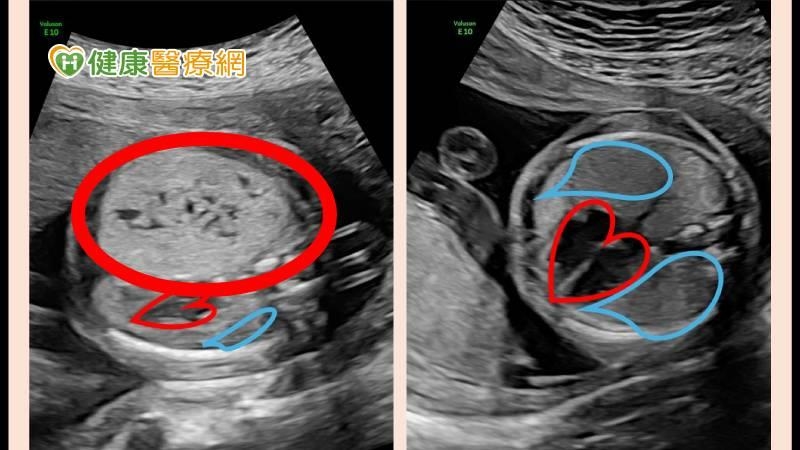

像黃女士就是在懷孕22週時因為產檢超音波發現胎兒肺部腫瘤,由宜蘭轉診至北榮,經高層次超音波檢查發現胎兒右側肺部有大型CPAM,大小約為有3.8 x 2.7 x 2.6 公分佔據肺部超過一半,並已將心臟與縱膈腔推向側邊。

不過到了懷孕後期,黃小寶的CPAM體積已經是原來的8-10倍,從3公分增長至7公分,佔據肺部超過70%,因此醫療團隊決定啟動生產計畫在36週進行剖腹,並在黃小寶出生後第一時間放置氣管內管進行呼吸支持,穩定後即由兒童外科醫師進行手術將CPAM切除,術後黃小寶恢復良好,進食、發展與一般同齡新生兒無明顯差異。